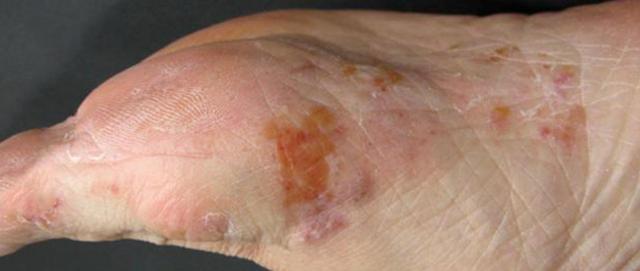

1.水疱型

好发部位:足底、足侧缘、手指侧面、指缝。

典型症状:皮肤出现散在或成群的深在小水疱,水疱壁厚、不易破裂,瘙痒感十分剧烈;水疱干涸后,会形成领圈样脱屑,处理不当易继发细菌感染,潮湿闷热天气症状会明显加重。